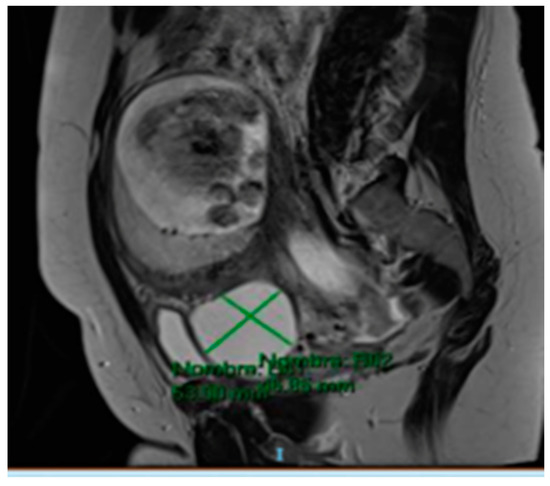

The MRI (Magnetic Resonance Imaging) scan showed 53 mm × 46 mm thin-walled cysts with a septum in the right paracervical area, another 27 mm × 20 mm cystic formation in the left hemipelvis (Figure 2 and Figure 3) and presacral 2 cm cysts containing a solid pole.

Figure 3. MRI scan compatible with 53 mm × 46 mm cystic formation in the right paracervical area.